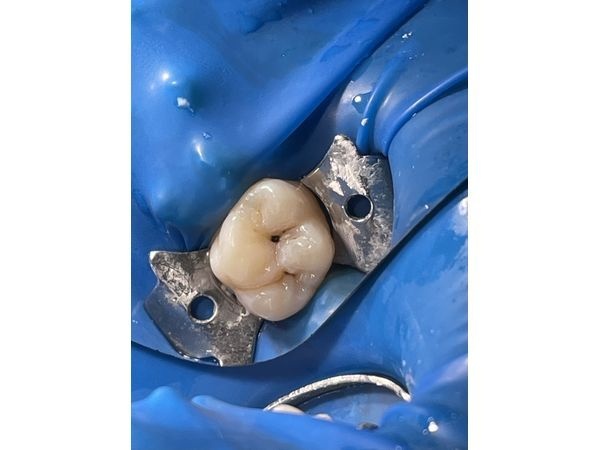

На жевательной поверхности правого верхнего моляра (зуба 16) в пределах средних слоёв дентина определялась кариозная полость, деминерализованная эмаль и плотный пигментированный дентин. Пульпа (нерв) реагировала на температуру. Реакция проходила сразу после устранения раздражителя, т. е. пульпа живая.

Зондирование по дентинно-эмалевому соединению вызывало боль. Простукивание и прощупывание переходной складки безболезненно. Слизистая оболочка полости рта и десна без патологических изменений. Оставшиеся ткани зуба плотные.

- изолировали рабочее поле системой коффердам, чтобы рабочие растворы не попали в полость рта;

- препарировали кариес;